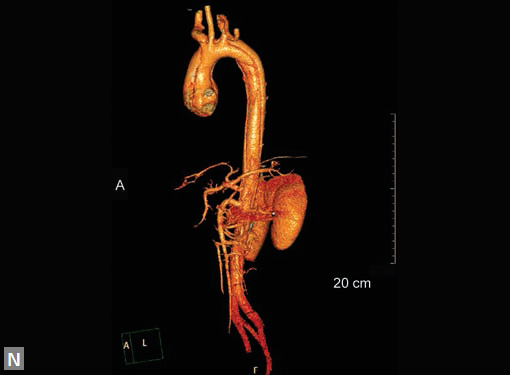

Connective tissue disease, hypertension and iatrogenic (Figs 19K to L) injury are the common causes for dissection. Radiologist not only establishes the diagnosis, also evaluates the extent of dissection, presence of thrombosis particularly in false lumen. In case of type A dissection, involvement of aortic root is determined. Relation of thrombosed lumen and ostia of coronary vessels, cephalad branches (Figs 19N, R to V) of aorta is determined. Most of the occasions membrane is demonstrated. Spiral nature of the membrane can be seen

Figs 19A to Y (A to C) Scannogram (A), plain (B) and contrast study (C) show partial anomalous pulmonary venous connection; (D to F) Heterotaxy; (G) Aortic occlusion; (H and I) Aortic stents; (J) Aortic dissection with ‘Benz’ sign due to second dissection within the true lumen; (K, L and M) Aortic dissection with thrombus in pseudolumen following catheter angiogram; (N) Aortic dissection involving common carotid arteries and subclavian artery; (O, P, Q and R) Aortic dissection with right renal artery arising from true lumen and left renal artery from false lumen; (S, T, U and V) Stanford B dissection with extension Y to iliac vessels; (W to Y) Aneurysmal dilation of ascending aorta